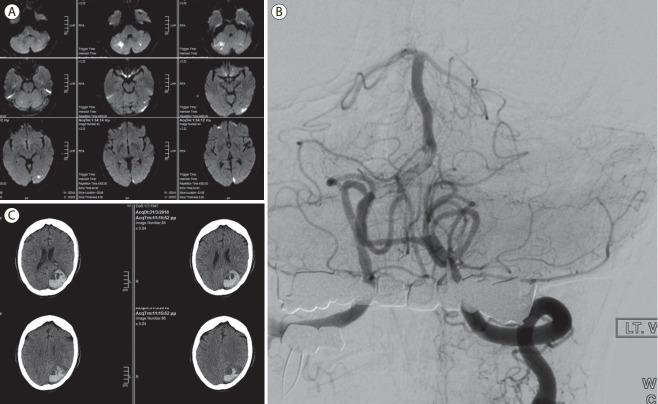

Abstract Image